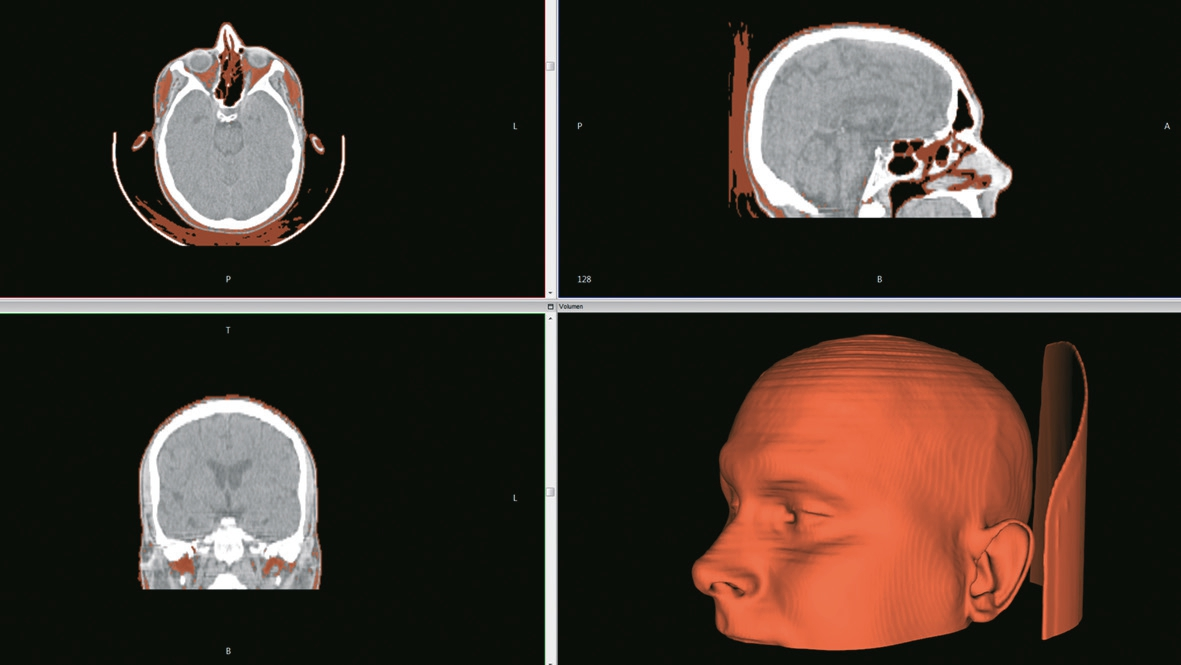

Moderne Scanner können hier einen erheblichen Vorteil liefern. Sie basieren entweder auf dem Einsatz von gebündeltem Licht (Laser), Streifenlicht oder 3D-Photogrammetrie. Davon abgesehen liefert auch die klassische 3D-Bildgebung in Form von Kernspin- (MRT), Computertomografie (CT) oder digitaler Volumentomografie (DVT) die Möglichkeit, 3D-Datensätze von Oberflächenstrukturen zu erstellen.

Datensätze aus der klassischen radiologischen Bildgebung ermöglichen grundsätzlich eine in den Dimensionen verlässliche und gleichwohl Unterschnitte berücksichtigende Datengrundlage. Allerdings stellen auch hier Bewegungsartefakte während der Aufnahmesequenzen ein Risiko für Dimensionsabweichungen dar. Weiter ist mit Rücksicht auf die oben genannten Methoden die Anwendung von Röntgenstrahlung für den ausschließlichen Zweck der Informationsgewinnung nicht zulässig. Auch der Einsatz von Magnetresonanztomografie (MRT) ist nicht zielführend – unter Berücksichtigung der Belastung des Patienten (Platz und Lärmverhältnisse) und der Kosten solcher Aufnahmen.